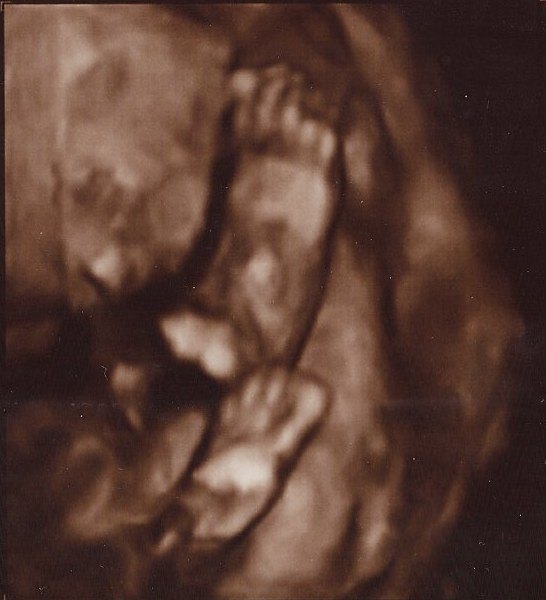

Det er så vildt at være til 3D scanning, det er som om, man er gravid på en helt anden måde bagefter

Ja, virkelig! Det er en hel anden måde at forholde sig til den lille på! Men når man ser billederne synes jeg man tænker "iih hun er stor", men hun er jo i virkeligheden stadig lillebitte. Lidt skægt